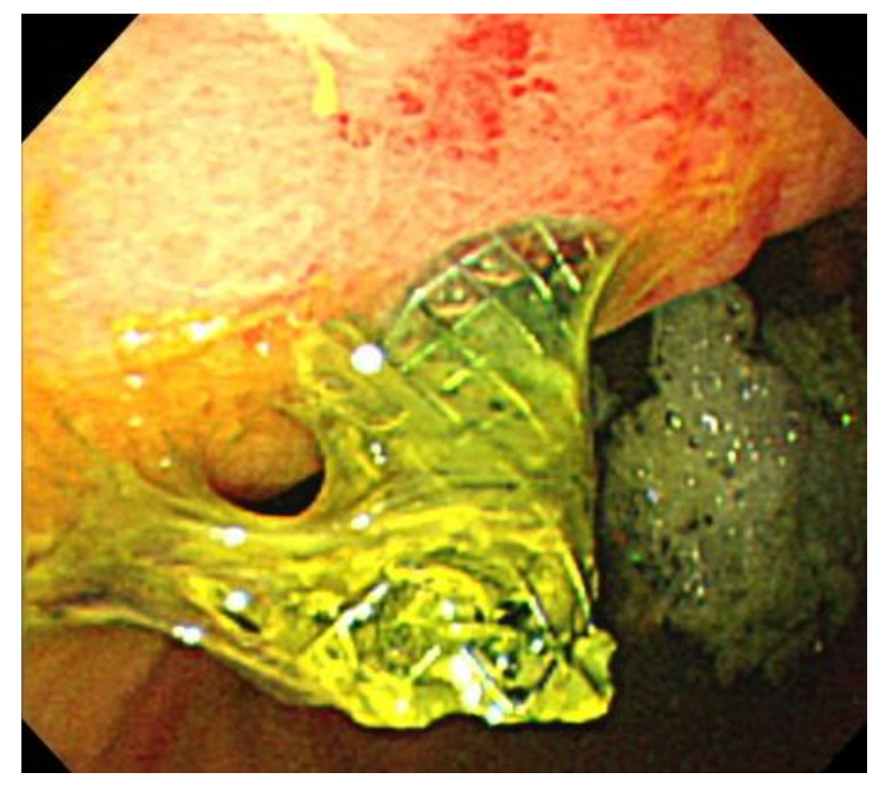

4. Discussion